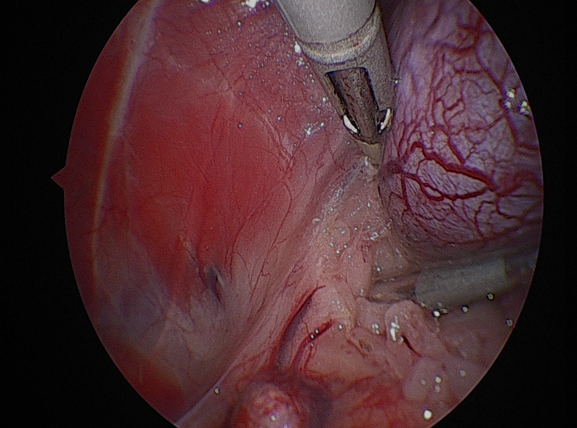

환자는 고령이었기 때문에 수술 후 통증과 회복 부담을 최소화하고자 복강경을 이용한 최소침습적 신장적출술을시행하였습니다.수술 과정은 다음과 같이 진행되었습니다.먼저종양이 위치한 신장을 후복막에서주변 조직과 분리하였습니다.

신장을 충분히 노출한 뒤, 신혈관을 순차적으로 처리했습니다.우선신정맥을 둔성으로박리하여 분리한 뒤, 클립으로 결찰하고절단하였습니다.

이어서 신동맥역시 같은 방법으로 둔성박리 후 클립 결찰후 절단하였습니다.

그 다음 신장에서 이어지는 요관을 따라 원위부로 추적하여 방광에 가까운 지점에서 둔성분리한 후 클립으로 결찰하고절단하였습니다.

이렇게 신장, 혈관, 요관이 모두 안전하게 분리된 것을 확인한 뒤, 적출된 신장을 수거 백에넣어 복강 내 오염 없이 외부로 제거하였습니다.

최소침습적 접근을 통해 조직 손상을 줄이고 통증을 최소화하면서, 종양을 안전하게 제거하는 데 중점을 두고 수술을 진행하였습니다.